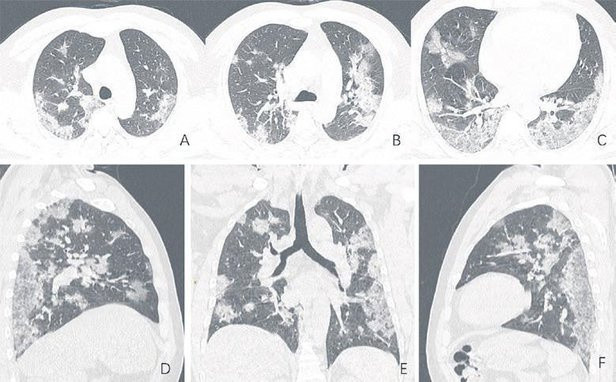

Bilgisayarlı tomografide akciğerlerde sıvı veya parçacık dolu keseler görüldü; bu durumun hastalık geliştikçe giderek kötüleşebileceği kaydedildi.

Hong Kong'un bulguları, Şubat 2020'nin başlarında Wuhan'ın önceden yapılan araştırmalarını doğruladı. Yakın tarihli bir çalışmada, Wuhan Üniversitesi Zhongnam Hastanesi'nden bilim insanları 140 koronavirüs hastasının akciğer taramasını analiz etti. Buna göre, her bir hastanın akciğerlerinde buzlu cam benzeri yapılar buldular.